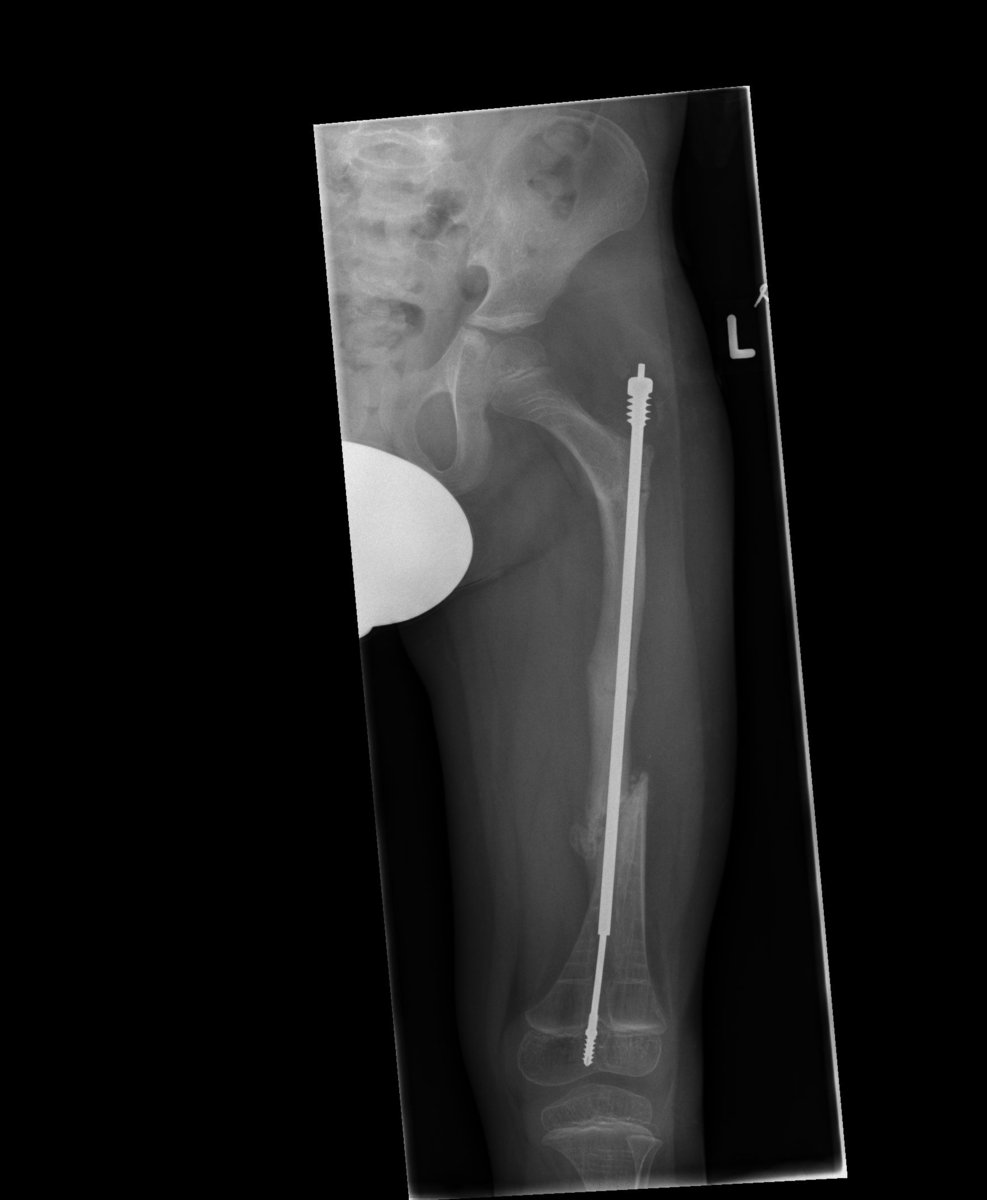

Der veränderte Knochenstoffwechsel führt bei sehr vielen Menschen mit OI zu einer erhöhten Neigung zu Knochenbrüchen. Viele haben außerdem mehr oder weniger ausgeprägte Verbiegungen der Knochen, meist der langen Röhrenknochen (Arme und Beine). Zu den Symptomen können außerdem eine Skoliose (Verkrümmung der Wirbelsäule) sowie Hypotonie (verringerte Muskelspannung), Schwerhörigkeit, Kurzsichtigkeit, überdehnbare Gelenke und Minderwuchs gehören. Manche Betroffene haben außerdem eine Dentinogenesis imperfecta, bei Ihnen kann es zur Verfärbungen und Brüchigkeit der Zähne kommen.